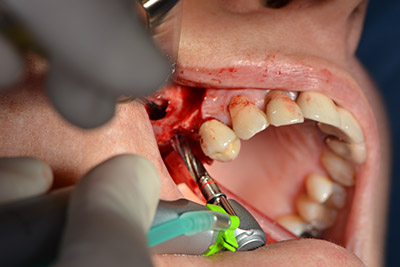

Последващите отвори се изборват с намалени обороти от 300 rpm. Implantmed демонстрира своя истински потенциал на този етап. Хирургичният протокол може да бъде зададен – различните позиции могат да бъдат лесно избрани чрез натискане на позиция “P” на педала (Фиг. 10 и 11).

Следващата програмирана позиция е поставянето на импланта и в нашата практика е предварително настроена на сила 32 Ncm (Фиг. 12).